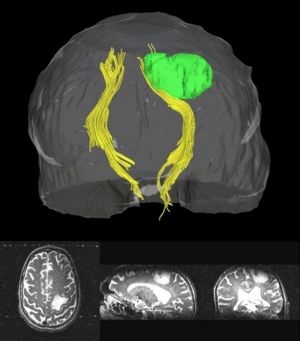

Thesis Results: Automatic Tractography Segmentation

Atlas creation and automatic labeling has been performed in high-quality DTI datasets from Susumu Mori. Images showing example segmentation results are below. Work is underway to apply this atlas to segment additional datasets to define regions of interest that may be used in the study of schizophrenia.

Selected anatomical regions, automatically labeled using the cluster atlas in 3 subjects.

Clustered fibers in the region of the corticospinal tract have been used to identify regions of interest for slice-by-slice measurements of its diffusion properties in normals and tumor subjects. A pilot study (with Monica Lemmond at Harvard Medical School and Stephen Whalen and Alexandra Golby at Brigham and Women's Hospital/HMS) has demonstrated changes in tumor-affected tracts (relative to the contralateral side) beyond the apparent tumor border. A larger study is currently underway.